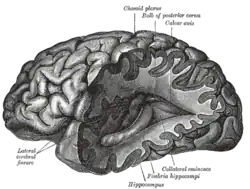

| Neuroimaging | |

|---|---|

.gif) Para-sagittal MRI of the head in a patient with benign familial macrocephaly | |

| Purpose | Indirectly (directly) image structure, function/pharmacology of the nervous system |

Neuroimaging is the use of quantitative (computational) techniques to study the structure and function of the central nervous system, developed as an objective way of scientifically studying the healthy human brain in a non-invasive manner. Increasingly it is also being used for quantitative research studies of brain disease and psychiatric illness. Neuroimaging is highly multidisciplinary involving neuroscience, computer science, psychology and statistics, and is not a medical specialty. Neuroimaging is sometimes confused with neuroradiology.

Neuroradiology is a medical specialty and uses non-statistical brain imaging in a clinical setting, practiced by radiologists who are medical practitioners. Neuroradiology primarily focuses on recognising brain lesions, such as vascular disease, strokes, tumors and inflammatory disease. In contrast to neuroimaging, neuroradiology is qualitative (based on subjective impressions and extensive clinical training) but sometimes uses basic quantitative methods. Functional brain imaging techniques, such as functional magnetic resonance imaging (fMRI), are common in neuroimaging but rarely used in neuroradiology. Neuroimaging falls into two broad categories:

- Structural imaging, which is used to quantify brain structure using e.g., voxel based morphometry.

- Functional imaging, which is used to study brain function, often using fMRI and other techniques such as PET and MEG (see below).